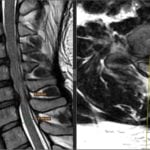

Printre acestea, RMN-ul (interpretare RMN) reprezintă o metodă de imagistică avansată utilizată pentru a identifica inflamația și modificările structurale la nivelul articulațiilor sacroiliace.

Aceasta oferă o imagine detaliată a țesuturilor moi și a structurilor osoase, permițând medicului să formuleze un diagnostic precis și să stabilească un plan de tratament adecvat pentru pacient.